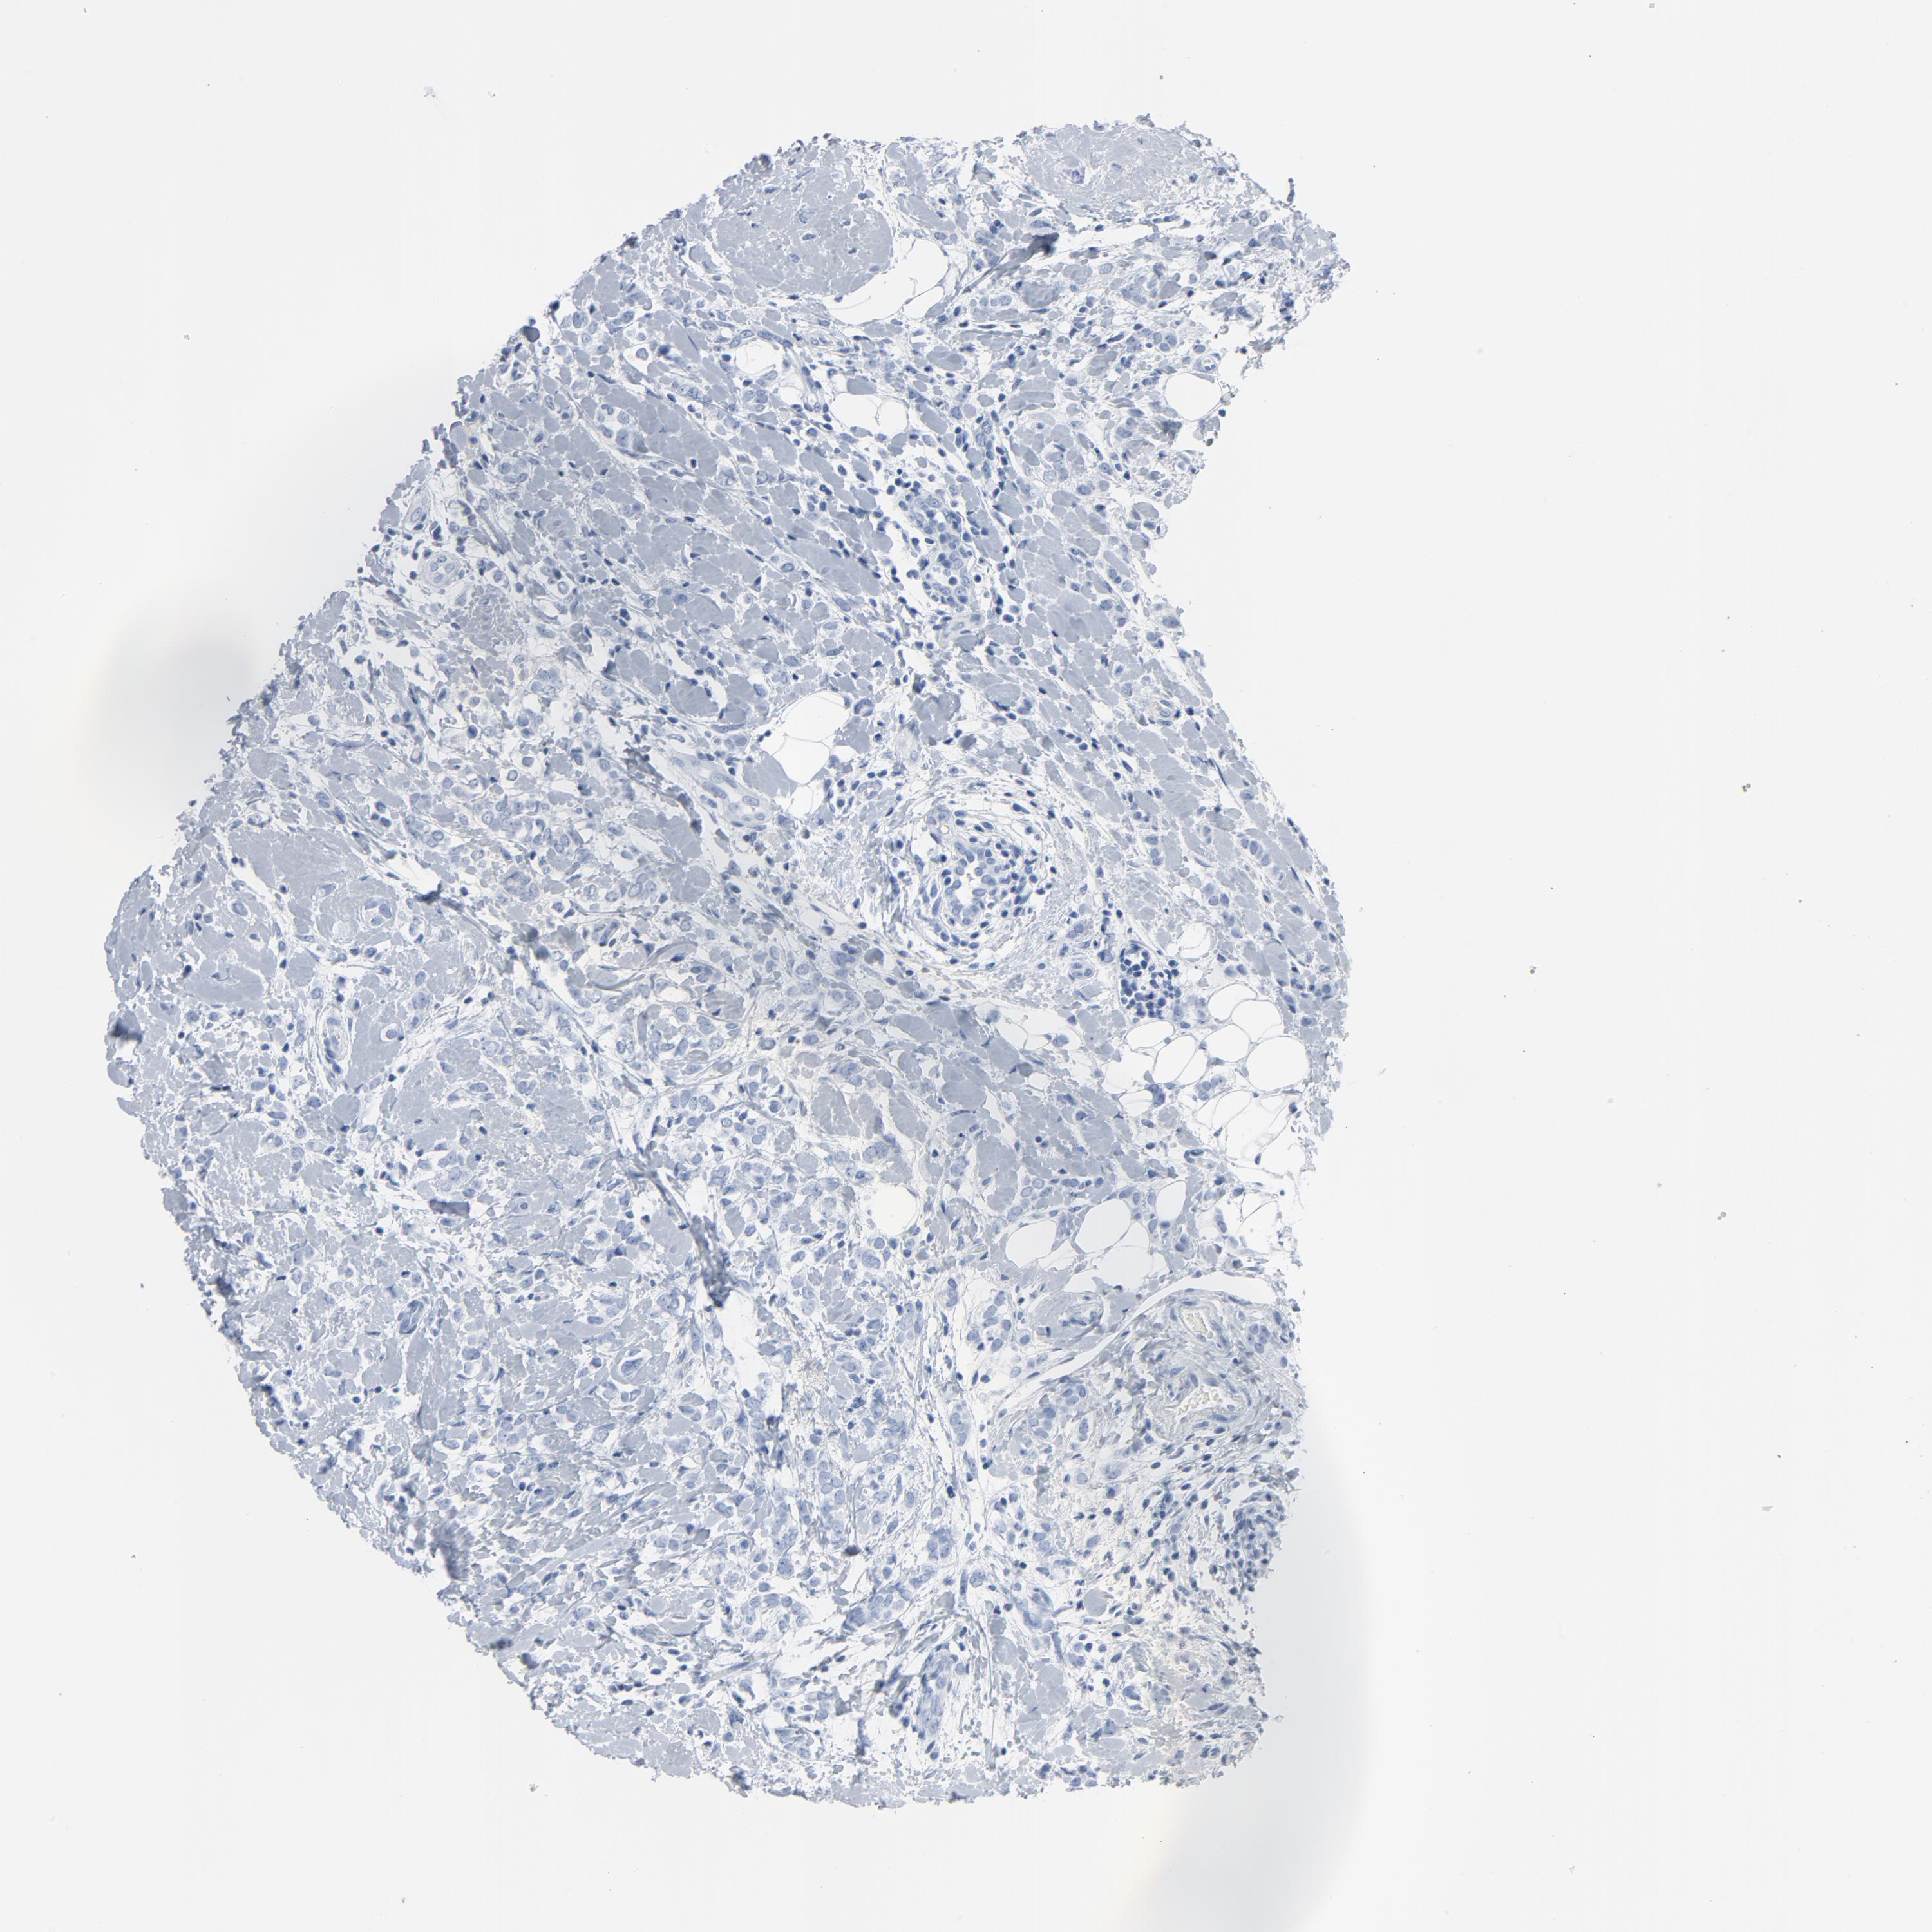

CANCER BREAST CANCER Show tissue menu

BRCA TCGA BRCA VALIDATION PROTEIN EXPRESSION

Breast cancer

Human cancer

Breast invasive carcinoma